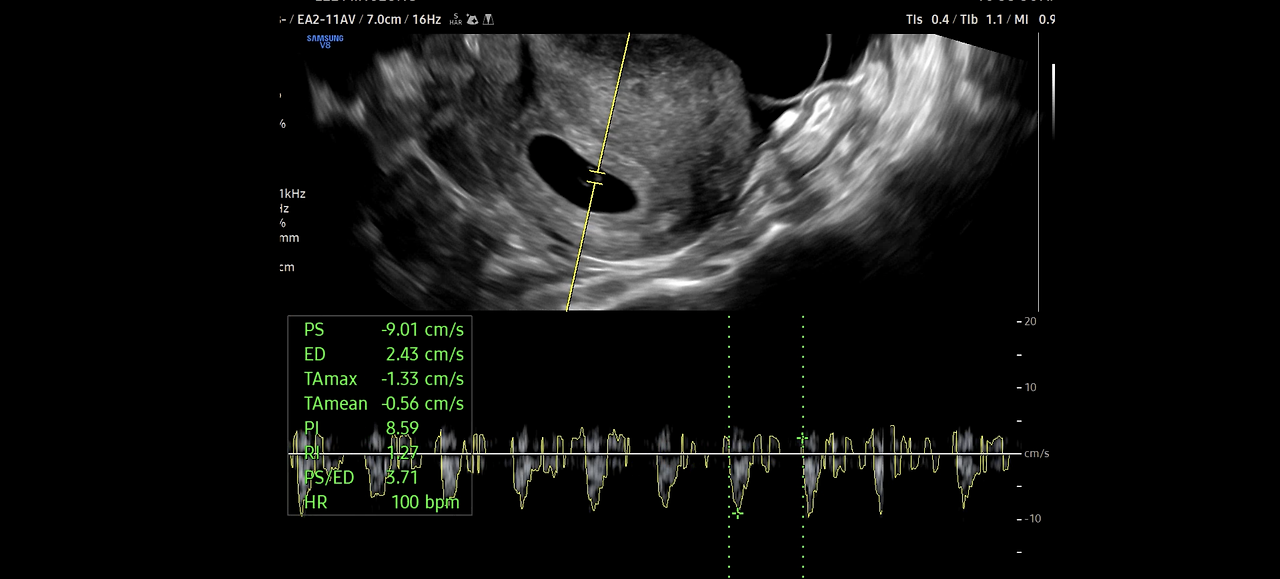

더 놀라운 사실은

어디에 어떻게 심장이 있어???

심장이 뛴다!!

97~100 bpm으로 심장이 뛰고 소리가 들리는데

아무리 다시 들어도 믿을 수가 없다.

5주 차에 본 것도 행운이고, 심장박동도 정상 범위다.